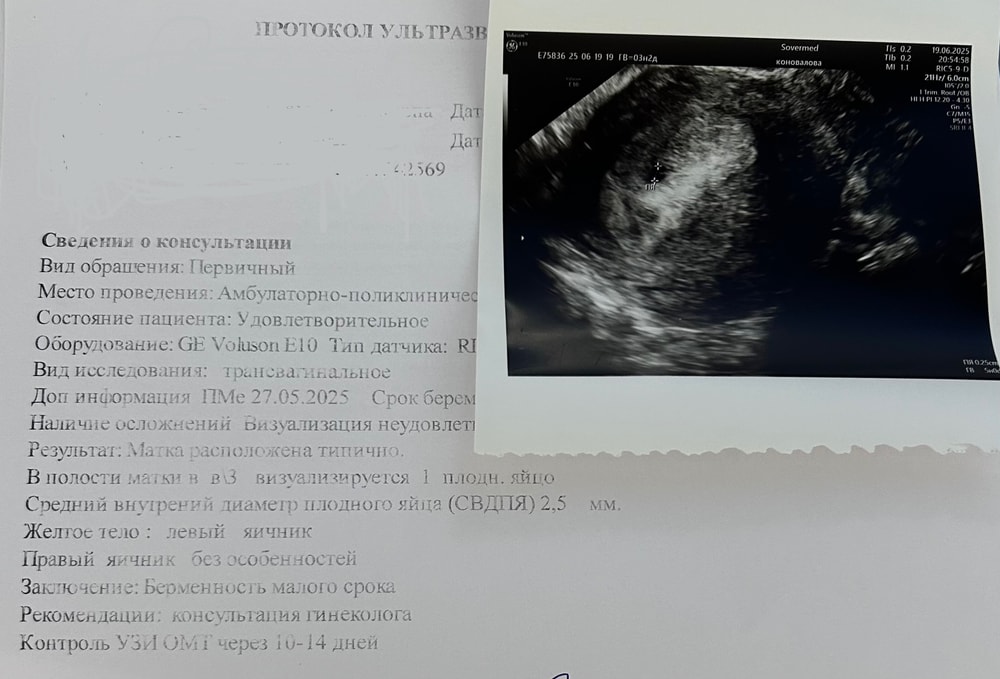

У вас до задержки на 11 дпо при хгч 28 пя нашли? Это из области фантастики,2,5 мм это скорее всего не пя, настоящее пя позже найдут,рано очень для обнаружения пя,с хгч 700-800 пя примерно такого размера только

Есть здесь истории,пошла на 15 дпо хгч 300 был нашли якобы пя 5 мм,что в принципе невозможно,потом пошла через неделю нашли пя 6 мм,типа практически не выросло,на самом деле 5 мм было не пя,а вот 6 мм через неделю было настоящим и все хорошо

Анна, да можно увидеть,но не при таком хгч,и в 4-5 акушерских недель,это 2,5-3 недели от овуляции ( т.е 18-21 дпо) ,а у вас 11 дпо это 2,4 от овуляции и акушерских нет даже 4 полных недель,от уровня хгч зависит размер пя,при очень маленьком хгч пя не видно ни у кого,а до задержки месячных можно увидеть,когда овуляция ранняя была и от овуляции прошло не 11-12 дней,а 18-20 уже и хгч соответственно не 30 и не 50, поэтому и находят,мне это читать не нужно,я 7 лет в этой теме,изучила все вдоль и поперек,у меня ксати в удачную беременность хгч 27 был на 10 дпо,рос очень быстро,УЗИ я сделала на 22 дпо хгч был высокий и было пя 8 мм только,если учитывать что на ранних сроках пя растет 1 мм в сутки,то появилось оно только на 14 дпо и было размером 1 мм,хгч ксати 300 был,но такой размер аппарат УЗИ не видет,я же не имею ввиду ничего плохого,просто рано очень

Я ходила на неполных 5 неделях, врач узи сказала, что надо идти после 5 недель, чтоб можно было точно сказать ПЯ это или нет. У меня в тот день увидели 3.5 мм вроде (оказалось что ПЯ все таки). Хотя хгч был маленький. Я говорю врачу - хгч плохо растет, маленький (400 что ли был), а врач сказала, что это не имеет значения, главное срок Б. В прошлый раз ПЯ 2 мм нашли при хгч 170.